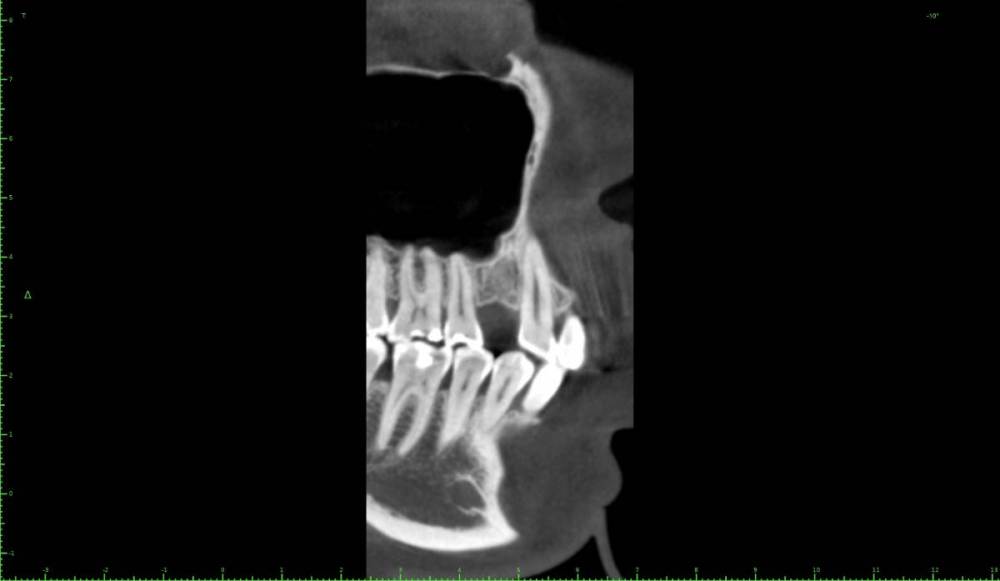

Женька Опубликовано 27 марта, 2021 Поделиться Опубликовано 27 марта, 2021 Коллеги, всегда задаюсь вопросом что делать в таких случаях? Пока никак сам не решал, потому что пациенты отказываются в пользу мостовидных и съёмных конструкций. Мини сосиска и и имплантат отсрочено с "мягким" синусом? Ссылка на комментарий